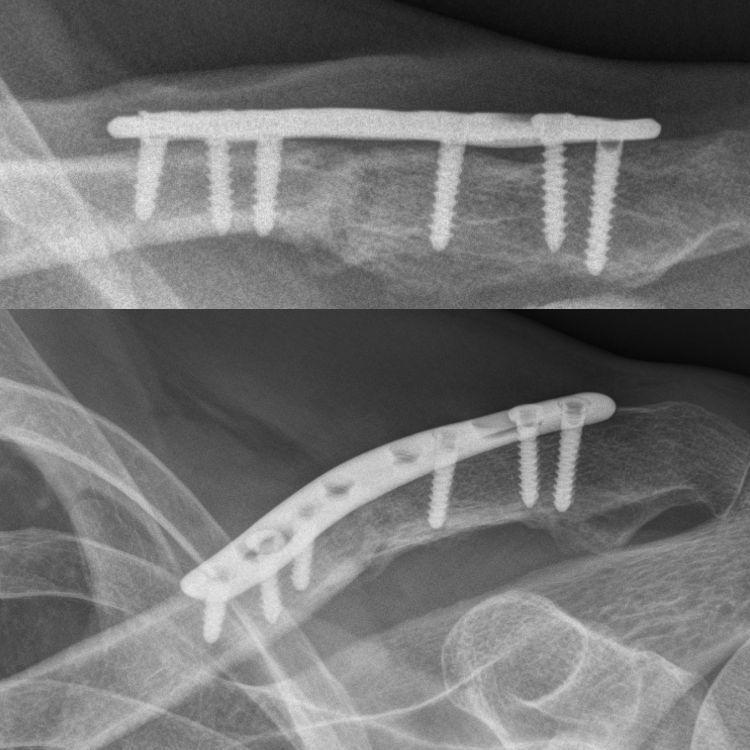

Hoe maak je een gebroken sleutelbeen Reparatie Het sleutelbeen ook wel bekend als het sleutelbeen hecht je borstbeen aan uw schouderblad. Daarom worden patiënten doorgaans gewaarschuwd dat een operatie aan een sleutelbeenbreuk later een tweede operatie kan vereisen om de hardware te verwijderen die wordt gebruikt om de breuk te herstellen. Hoe een kapotte GM-sleutelhanger te repareren.

Hoe kan ik een auto-oplader te repareren. Ik had 3 kapotte sleutelaanhangers elektronica was goed maar de behuizing was gebroken bij de ring. In sommige gevallen wordt een sleutelbeenbreuk behandeld door middel van een operatie.

Zelfs zo betreur ik niet mijn keuze om een chirurgische ingreep na te streven. Als dit nodig is zal de specialist van polikliniek dit met u bespreken. Pas op dat het verwijderen van de plaat moet losschroeven verschillende schroeven en er is een kleine kans op het sleutelbeen opnieuw te breken op een schroefgat voordat het weer geneest.